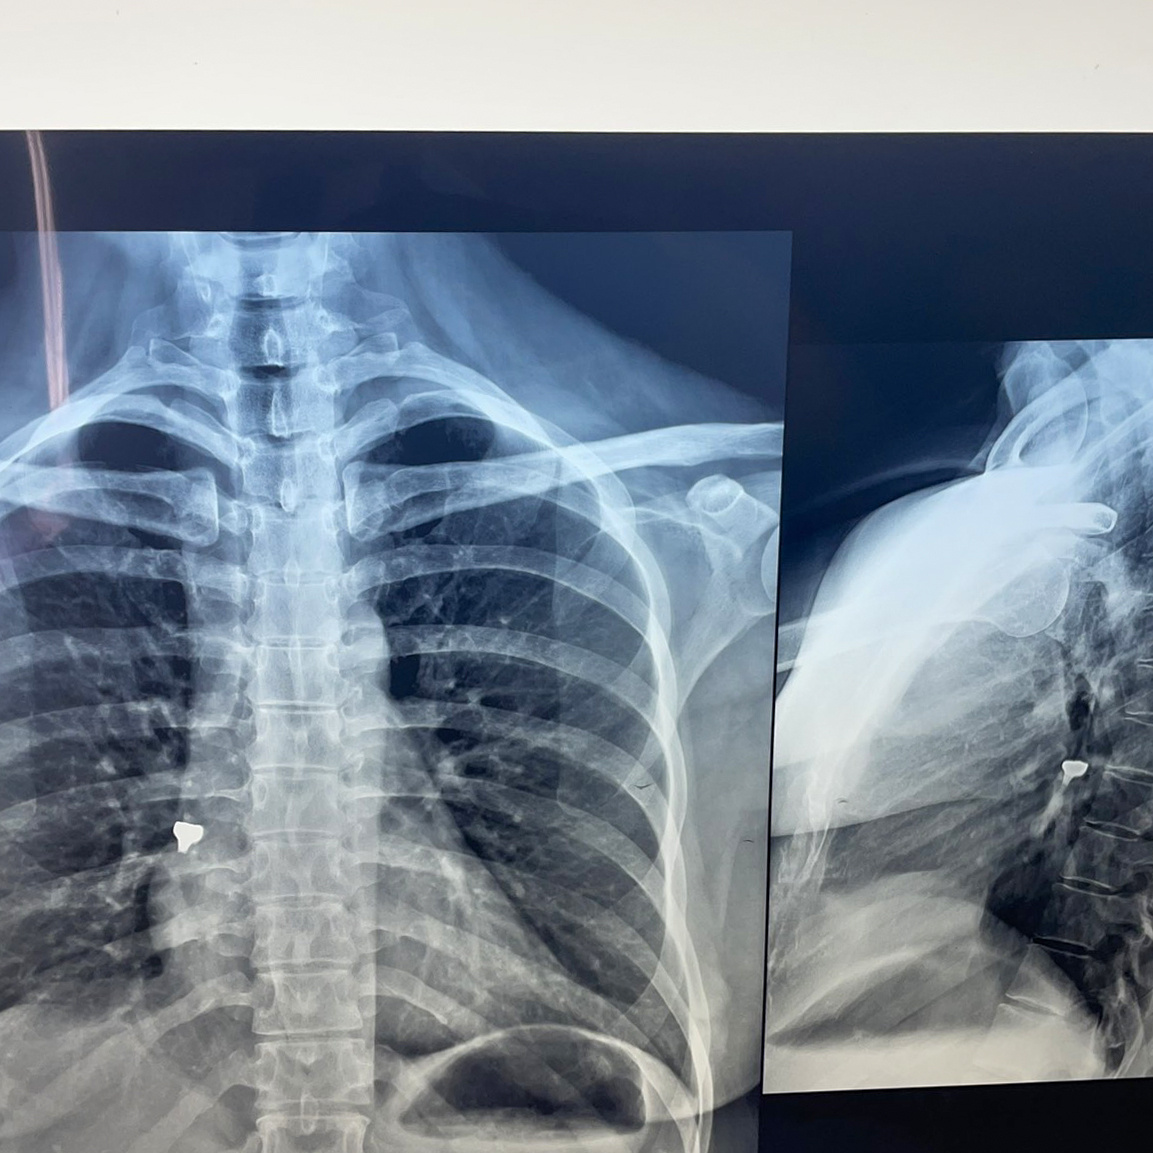

Kurora e dhëmbëve pacientes i kishte depërtuar në rrugët e frymëmarrjes duke bërë që t’i keqësohet gjendja shëndetësore dhe duke e rrezikuar seriozisht shëndetin e saj, me simptoma të frymëmarrjes së vështirësuar dhe kollitje.

“Pacientes A.D. ( 1986), nga Gjakova, e cila gjatë ndërhyrjes stomatologjike tek stomatologu, kishte gëlltitur një kurorë dhëmbësh, duke i depërtuar në rrugët e frymëmarrjes i ishte keqësuar gjendja shëndetësore, duke e rrezikuar seriozisht shëndetin e saj, me simptoma të frymëmarrjes së vështirësuar dhe kollitje. Me urgjencë ishte sjellur në Klinikën e Pulmologjisë, ku mjekët e klinikës konstatuan se duhet të bëhet ndërhyrje urgjent përmes bronkoskopisë, duke hequr kurorën nga rrugët e frymëmarrjes dhe duke i shpëtuar jetën”, thuhet në njoftimin./Arbresh.info/